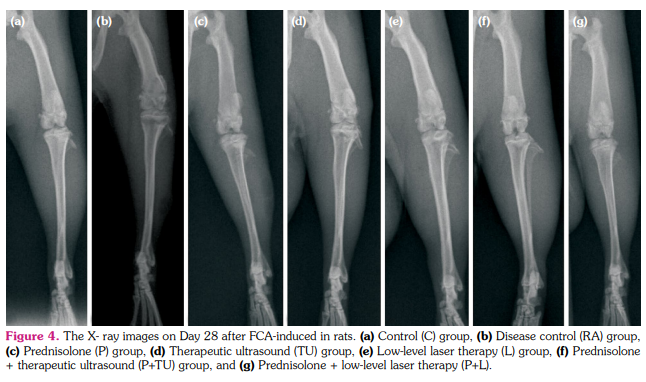

Radiological analysis

Before the begging of the study, the joints of rats were determined to be free of any radiological abnormality. The rats were anesthetized with sevoflurane and were positioned ventrodorsally on a table and X-ray image was obtained in the posterior-anterior view of the right knee joints with a stationary X-ray machine (Mex-100, Medical ECONET, Oberhausen, Germany) at 12 mA/s, 40 kV on Days 14 and 28. Two different blind observers performed radiological visual scoring, and visual scoring values were calculated based on the following conditions;[23] erosions: 0-3 (none, mild, moderate, severe); joint space narrowing: 0-3 (none, minimal, moderate, severe); joint space destruction: 0-3 (none, minimal, extensive, ankylosis).

Evaluation of radiological score

The radiological abnormality was not observed any time points in C groups (on Days 14 and 28 radiological score= 0, Table 1). The radiological score was not significantly different among groups on Day 14 (p>0.05, Figure 4). Compared to the RA groups (1.98±0.6), the mean radiological score was lower TU (1.55±0.5), P (1.45±0.5), L (1.45±0.1), P+TU (1.11±0.5), and P+L (1.05±0.3) group on Day 28 (Figure 4). The P+TU and P+L groups significantly decreased radiological scores at the end of the study (p<0.05, Figure 5). The P, TU, and L groups also decreased radiological scores, but were not statistically significant (p>0.05, Table 1).

During the process of adjuvant induced RA, joint inflammation is caused by the infiltration of immune cells, synovial hyperproliferation, and the over production of proinflammatory cytokines, such as TNF-α and IL-1β, following causing cartilage and bone damage.[38] Moreover, Uddin et al.[39] reported that the TU stimulation prevented cartilage damage by inhibiting the IL-1β and stimulating chondrocyte migration, proliferation, and differentiation. The proinflammatory cytokines may cause bone erosion indirectly by promoting differentiation of osteoclast precursors and afterward by activating osteoclasts.[40] Therefore, the radiological examination is a useful measure of disease severity, as well as progression in RA.[41] Our study showed that the RA groups’ radiological score was higher than all treatment groups. On Day 28, the P+TU and P+L groups radiologically reduced the severity of arthritis compared to Day 14, possibly by inhibiting the infiltration of proinflammatory cytokines. This result is consistent with our histopathological findings.